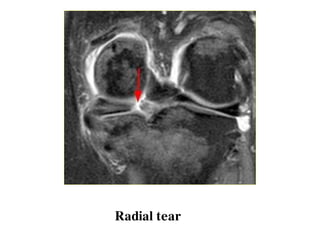

o Radial tear

Radial tear